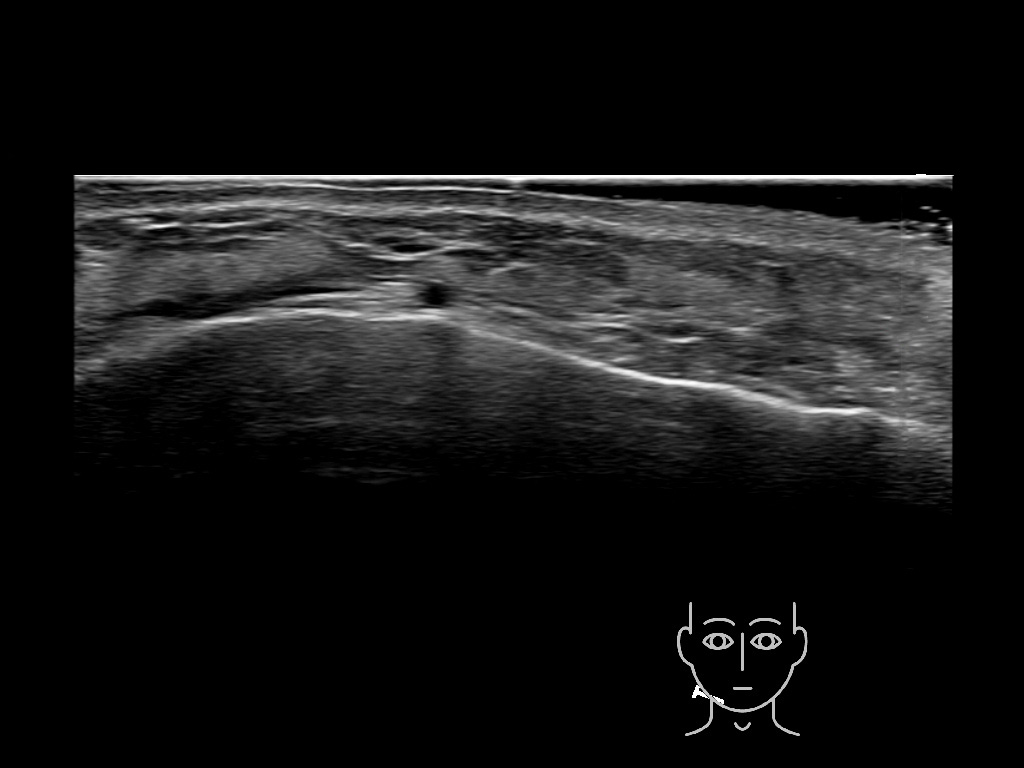

Draw in the second image below where the fillers are located. To check if your answer is correct, swipe the first image to the right.